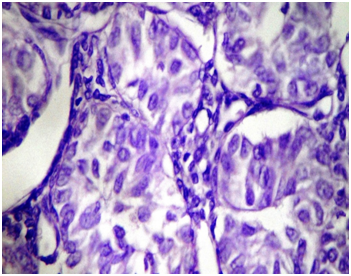

A two years old girl presented with history of urinary retention since 2 months. It was associated with decrease urinary output and painful micturation since 1 month. She also had a history of gradual abdominal distention with mild abdominal pain. She is a product of consanguineous marriage with death 2 of her preceding sibling due to unknown reasons at age of 3 months and 2 years. Her general physical examination was normal. Her abdominal examination showed massive abdominal distention with positive fluid thrill and shifting dullness. A rounded, fixed mass felt at the pelvic area with smooth surface. Her rectal examination showed tenderness at the anterior rectal wall. She had normal breast and genetalia. Normal blood & urine tests. Abdominal ultrasound showed a mixed echogenicity mass measuring 11.5x6.7cm with both solid and cystic components arising from the pelvic area with gross ascites. Contrast enhanced CT scan shows massive ascites and a large, heterogenous, solid cystic mass in lower abdomen & false pelvis (11x8.1x7.5cm); originating from the left adenxa with no internal calcification. There was associated with abdomen-pelvic ascites. Rest of abdominal viscera, peritoneium and lymph nodes were unremarkable. Her Alfha fetoprotein and bHCG were normal. On exploratory Laprotomy 1 liter of Ascitic fluid was drained with samples sent for analysis. Left salpingo-opherctomy was done as the mass was originating from the left ovary Figure 1. Uterus, right ovary and lymph nodes were grossly normal. Peritoneal fluid cytology was negative for malignant cells. Grossly the mass was having mixed cystic and solid areas, weighting 1.3kg with some focal areas of hemorrhage Figure 2. Histopathological examination Microscopic features show diffuse sheets and macrofollicular pattern of tumor cells. The malignant cells were polygonal and small. The cytoplasm was abundant and amphophilic. The nuclei were atypical without grooves and show conspicuous nucleoli at places. Mitotic activity was more than 10 cells/10 hpf. Large tumor cells with extensive lutenization were seen focally, presenting the cal component of ovarian stroma that is compatible with Juvenile granulosa cell tumor Figure 3. Immuno-histo-chemistry was positive for Inhibin and CD99 and negative for EMA, CD117 and alpha feto-protein. Bone scan and chest radiographs were unremarkable. Based on FIGO staging system this patient is stage IA. On 3 months follow up patient is doing well and her urinary retention relieved, however she is on long term follow up due to late recurrence.

Figure 3H & E stain on Light Microscopy (400 magnification) of JGCT show macrofollicles of tumor cells. Neoplastic cells are polygonal with abundant amphophilic cytoplasm. The nuclei are without grooves and may contain conspicuous nucleoli.